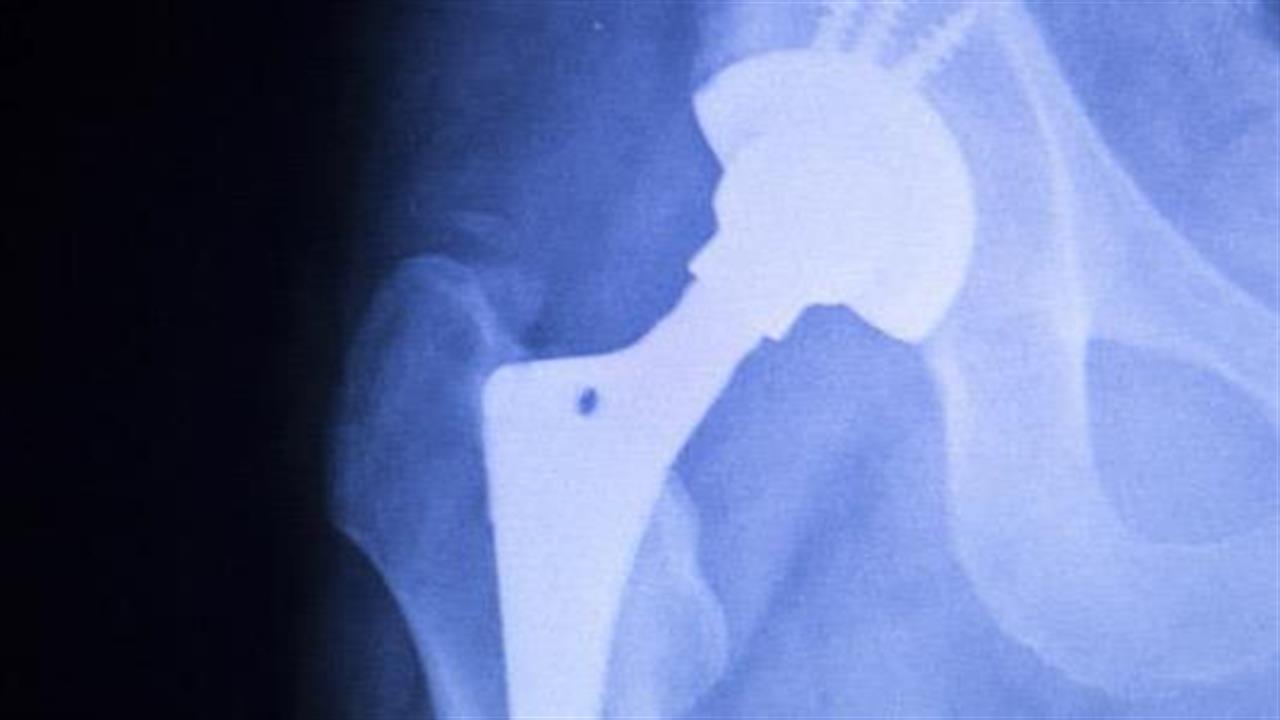

Πολλές ζωές θα μπορούσαν να σωθούν, αν ασθενείς με κάταγμα ισχίου χειρουργούνταν εντός 24 ωρών, αναφέρει νέα έρευνα.

Η έρευνα εστίασε σε 241.446 ασθενείς που εισήχθησαν στο νοσοκομείο με κάταγμα ισχίου, μεταξύ Ιανουαρίου 2011 και Δεκεμβρίου 2014, και το ποσοστό θνησιμότητας 30 ημέρες μετά την εισαγωγή.